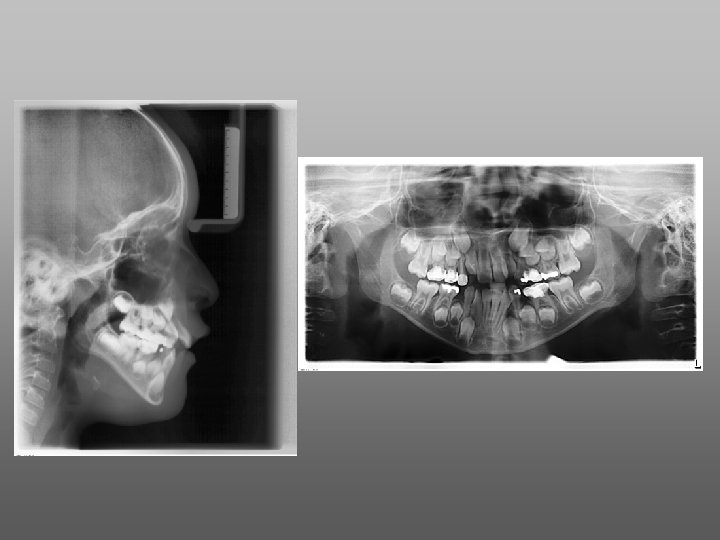

Aplicaciones clínicas de la Radiografía Digital • Diagnóstico • Periodoncia R. D. • Endodoncia • Cirugía • Implantología SOFTWARE